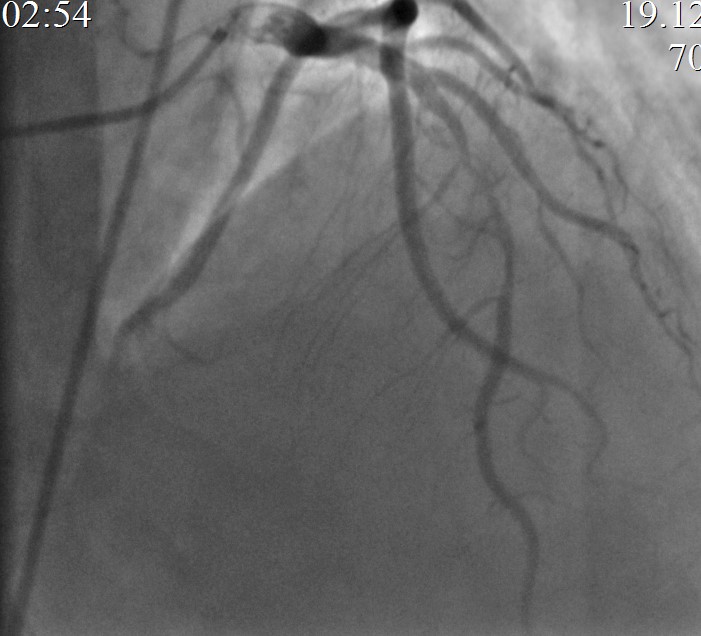

На КАГ: ПМЖА – устье кальцинированный стеноз 50%, среднем отделе кальцинированный протяженный стеноз 99% с переходом в кальцинированную окклюзию, дистальный кровоток TIMI 0-I. (в последующем наблюдается спонтанная реканализация перед ЧКВ, с кровотоком TIMI II-III). Дистальные отделы заполняются фрагментарно ретроградно из ветвей ПКА. ПКА проксимальном отделе стеноз 40%.

Учитывая анамнез заболевания, данные настоящей КАГ, принято решения выполнить баллонную ангиопластику со стентированием инфаркт-зависимой артерии.

Произведена баллонная ангиопластика со стентированием целевой зоны коронарным стентом (BMS) 3.0х37,0мм.

Контрольная КАГ: просвет ПМЖА в зоне вмешательства полностью восстановлен, остаточный жесткий кальцинированный стеноз среднего отдела стентированного сегмента 50%, антеградный кровоток TIMI III на протяжении по всем артериям.